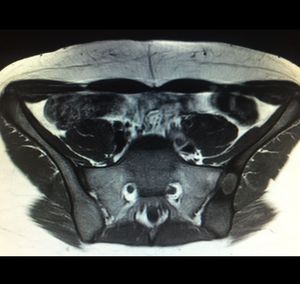

What is The diagnosis?

Magnetic

Resonance

Hipbone